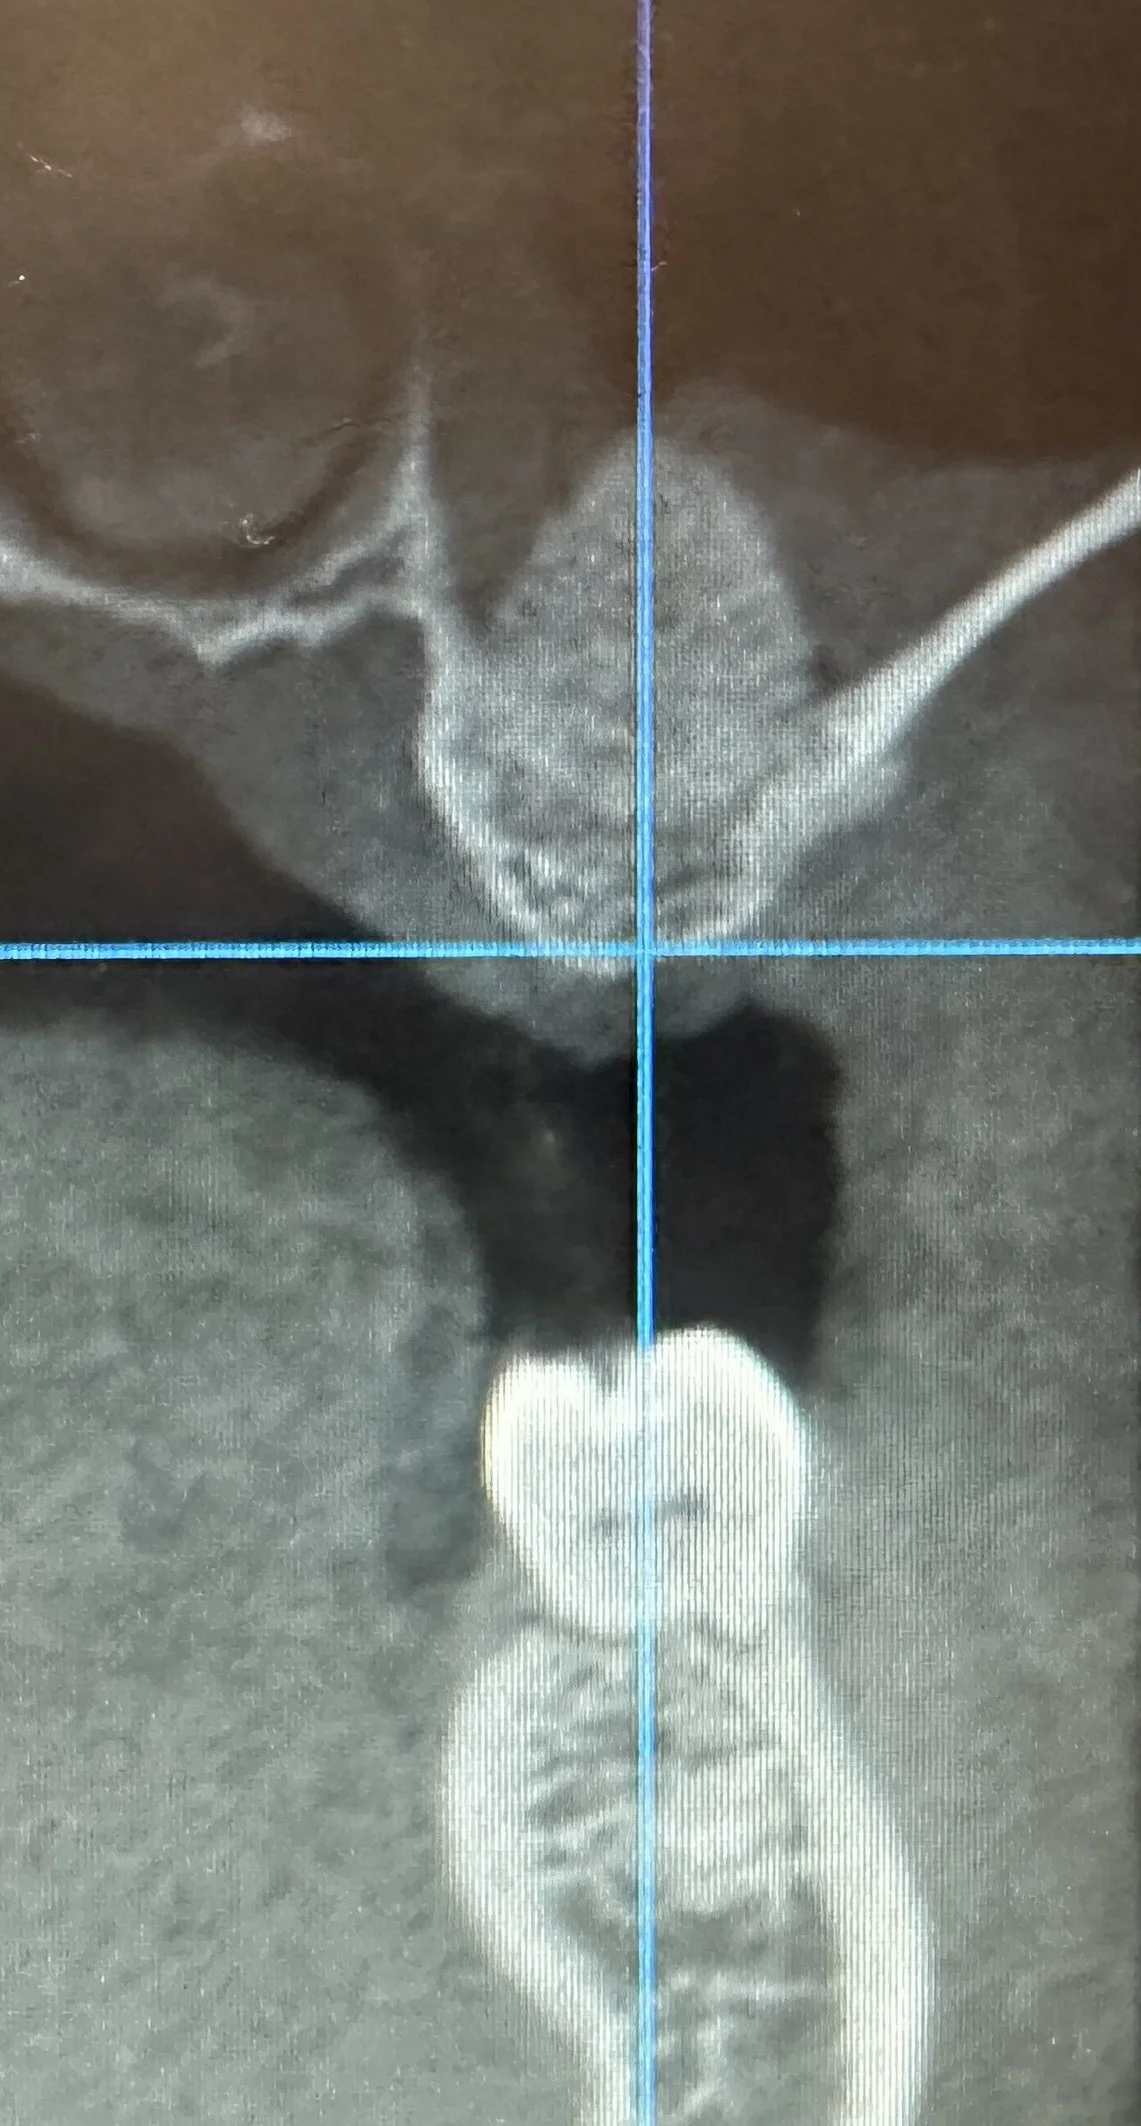

The procedure was indicated due to limited vertical bone height — approximately 2 mm as seen in the initial CT scan — which prevented immediate implant placement.

Post-operative imaging shows a significant increase in vertical bone height within the grafted area, creating a stable and predictable foundation for implant placement.